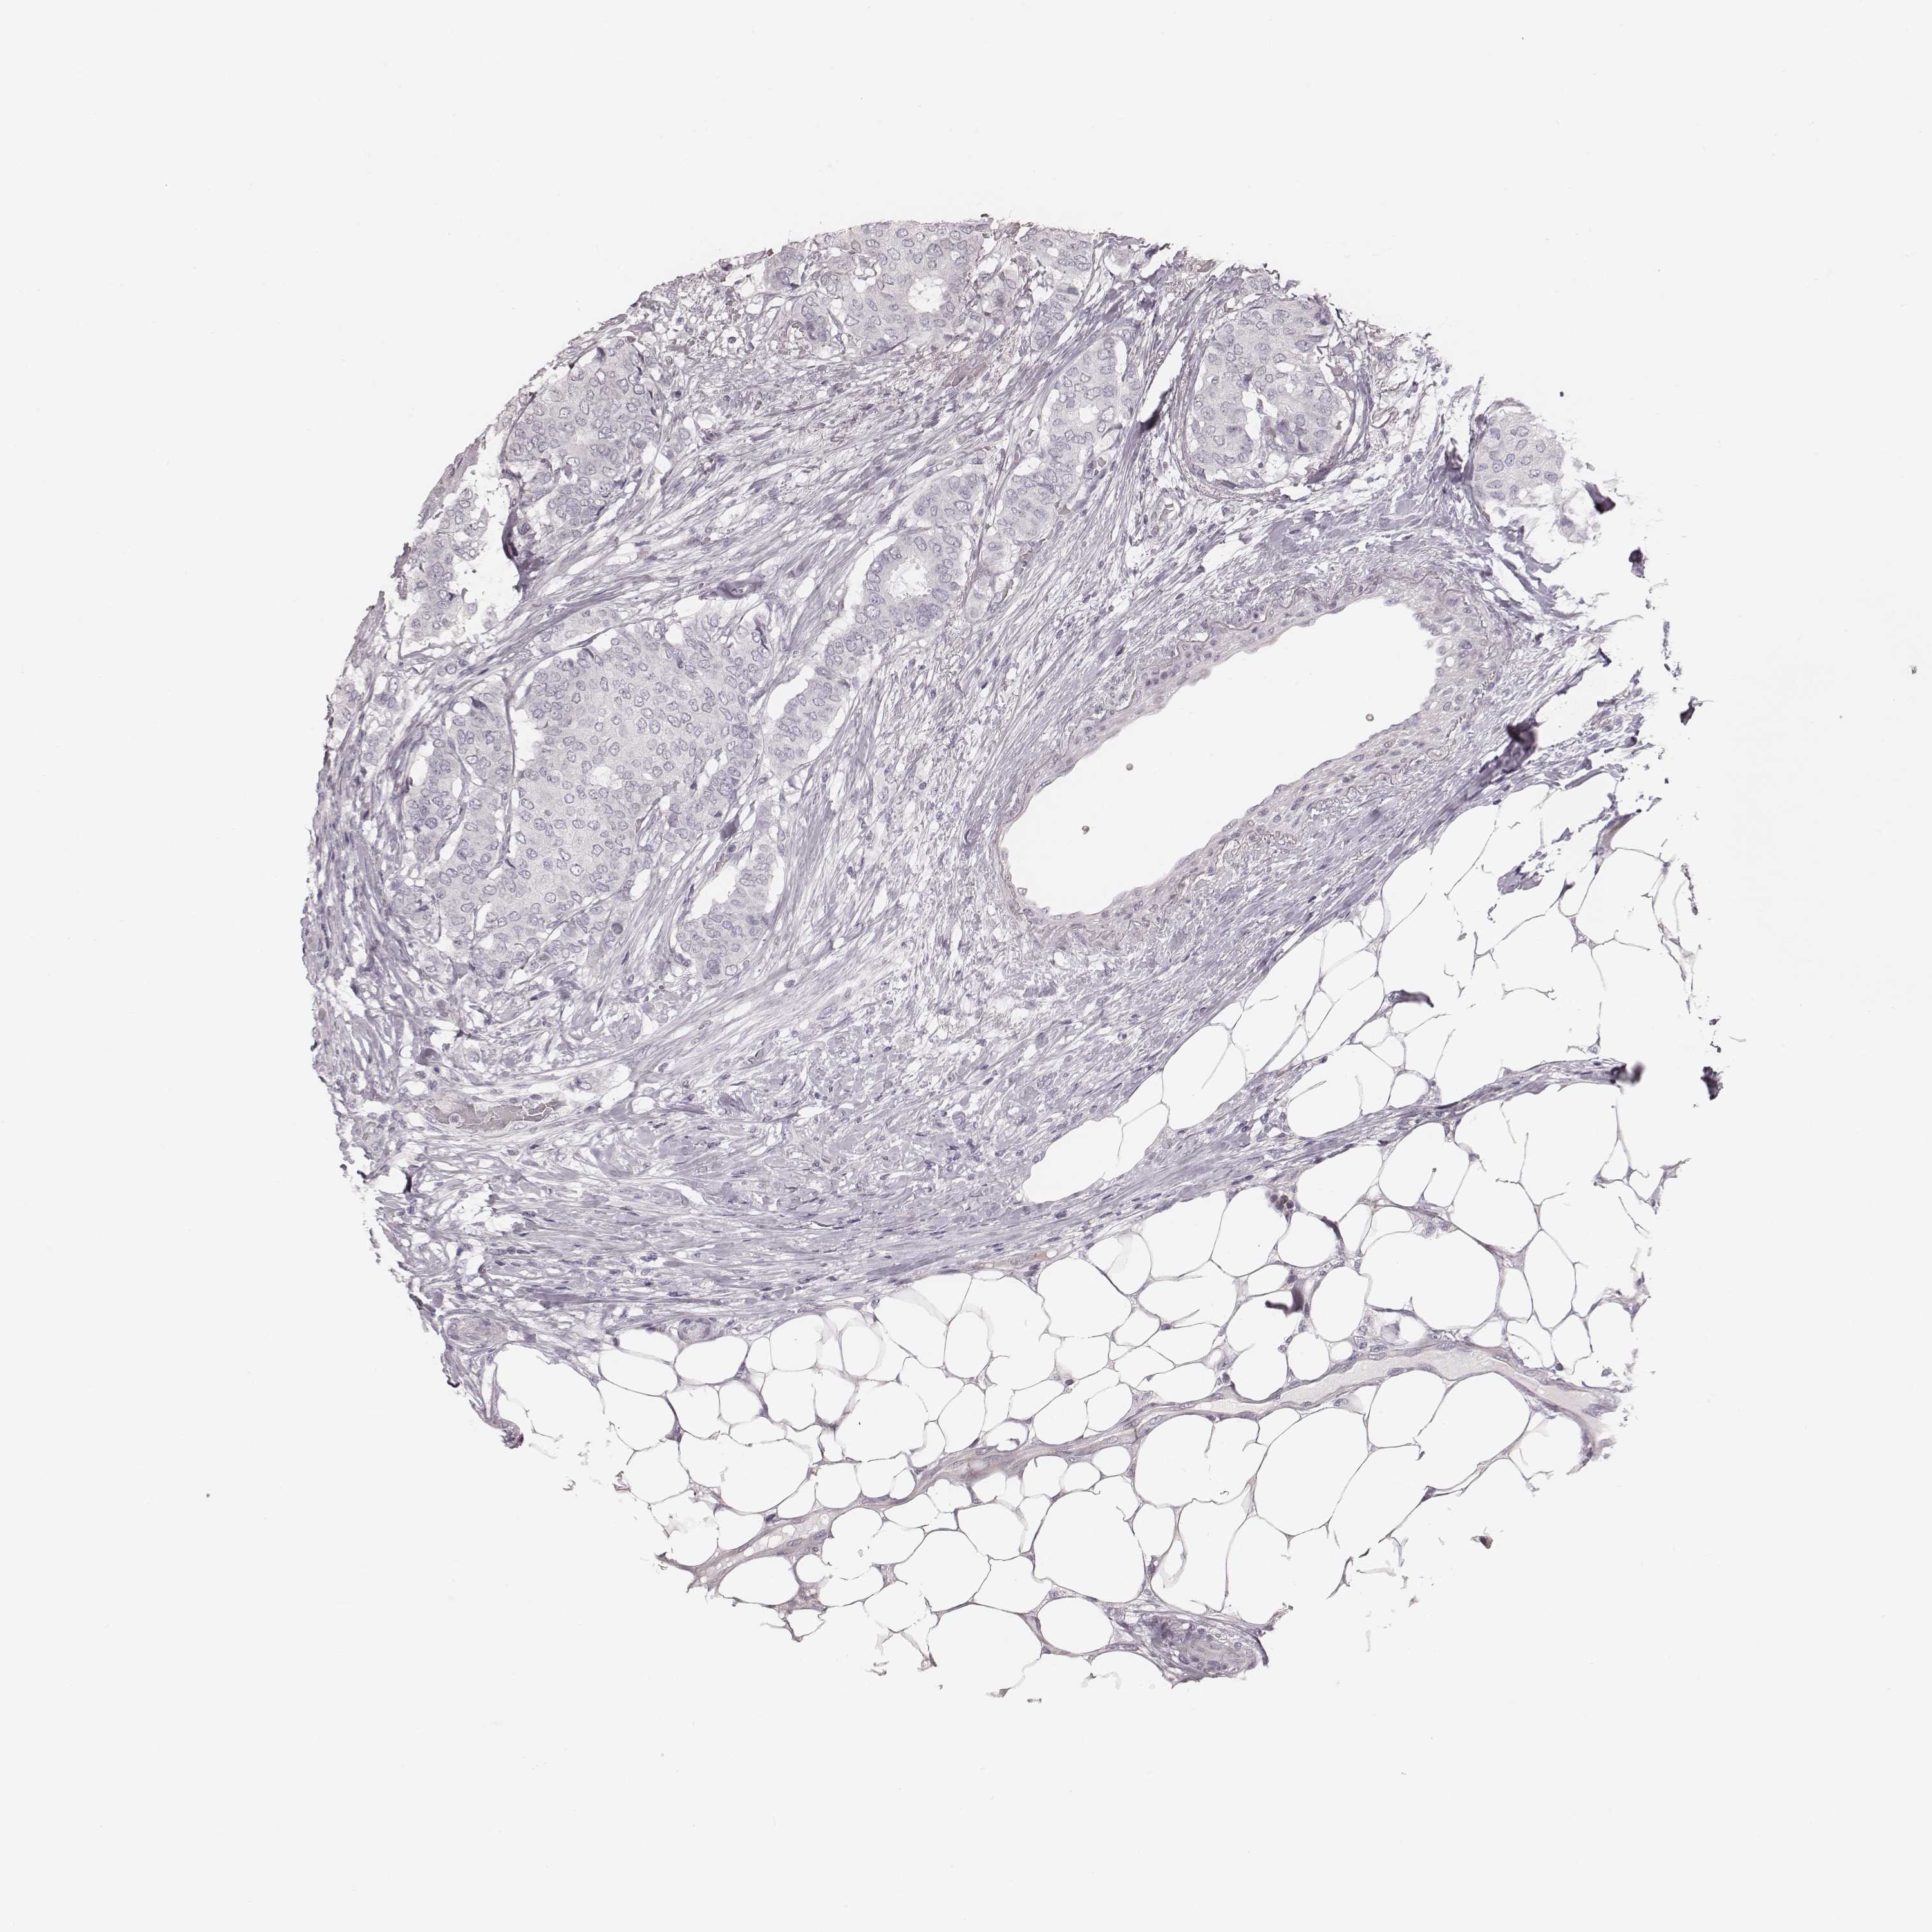

BRCA TCGA BRCA VALIDATION PROTEIN EXPRESSION

ANTIBODIES

AND

VALIDATION